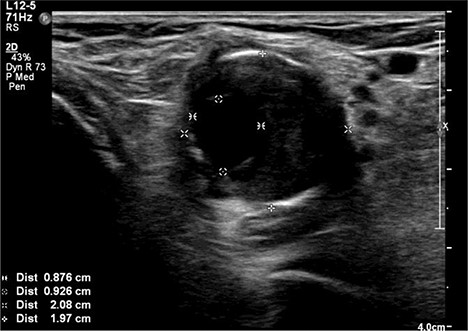

A 92-year-old female, independent from home, presented after multiple falls due to a four-month history of left foot drop. The foot drop had gradually worsened to the point that there was complete paralysis of ankle dorsiflexion and was associated with significant oedema of the foot. On examination, there was a large pulsatile mass in the popliteal fossa bilaterally. All peripheral pulses were palpable without any signs of ischemia. The most striking examination finding was complete paralysis of left ankle dorsiflexion with 0 out of 5 power. Ultrasound revealed that there were (Fig 1) bilateral popliteal artery aneurysms, which was larger on the left, causing displacement and impingement of the common peroneal nerve at the knee crease (Fig 2). Further computed tomography angiogram demonstrated an unruptured left PAA measuring 22 × 21 mm in maximal dimension over a distance of 24 mm (Fig 3). Intraluminal thrombus was also noted with 60% luminal stenosis. Distally, the arteries were heavily calcified with two-vessel runoff at the ankle. An emergency endovascular repair of the left PAA was performed by using 8 mm × 15 cm and 7 mm × 10 cm Gore Viabahn stents (Fig 4). The stents were deployed after a balloon-angioplasty and adequate decompression of the aneurysm was achieved. The postoperative period was uneventful, and patient’s pre-existing aspirin was continued. The leg and foot oedema improved rapidly over the subsequent few days. At follow-up in 12 weeks, the patient showed some return of motor function of the ankle and was walking with ankle splint. Her left leg remained well perfused with palpable pulses.

Ultrasound image of left popliteal artery aneurysm containing intramural thrombus, measuring 21 × 20 mm.